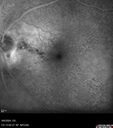

Peripapillary CNVM No Treatment33 views85 year old with peripapillary CNVM watched for many years.

Peripapillary CNVM No Treatment32 views85 year old with peripapillary CNVM watched for many years.

Peripapillary CNVM No Treatment29 views85 year old with peripapillary CNVM watched for many years.

Peripapillary CNVM No Treatment28 views85 year old with peripapillary CNVM watched for many years.

Peripapillary CNVM No Treatment26 views85 year old with peripapillary CNVM watched for many years.

Peripapillary CNVM No Treatment25 views85 year old with peripapillary CNVM watched for many years.

Peripapillary CNVM No Treatment24 views85 year old with peripapillary CNVM watched for many years.

Peripapillary CNVM No Treatment22 views85 year old with peripapillary CNVM watched for many years.

Peripapillary CNVM No Treatment21 views85 year old with peripapillary CNVM watched for many years.